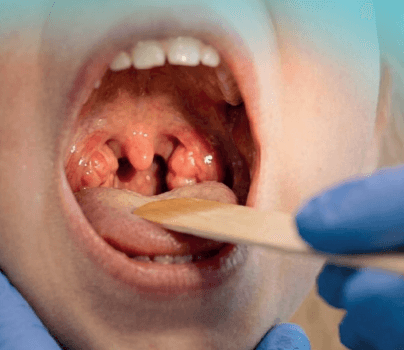

I disturbi respiratori ostruttivi rappresentano una delle sfide più frequenti nell’Otorinolaringoiatria pediatrica. Oggi, l’obiettivo

del chirurgo non è solo l’efficacia risolutiva, ma il raggiungimento della massima sicurezza clinica. Il principale valore aggiunto

della tecnologia Coblator nel trattamento della patologia adenotonsillare risiede nella drastica riduzione dell’incidenza di

emorragie post-tonsillectomia, garantendo al contempo una miniinvasività che si traduce in minor dolore post-operatorio e in

una rapida ripresa funzionale del piccolo paziente.